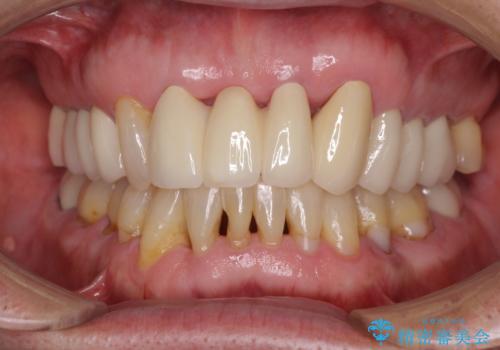

![[MTMを行い歯の神経を保存] 歯周補綴ブリッジの症例 治療後](https://seimitsushinbi.jp/wp/wp-content/uploads/2021/04/75330aaa19199048b71f28658fe46b5b-1-500x350.jpg?v=1618452202)